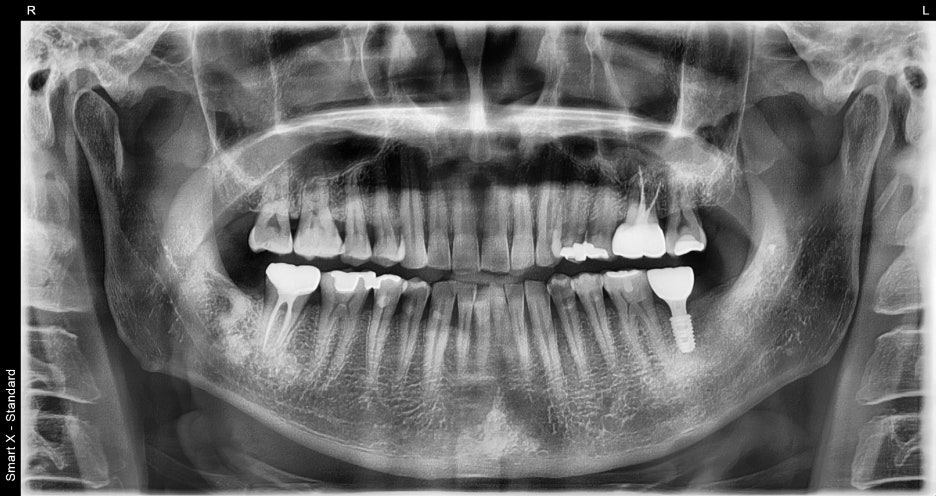

④ Prosthesis (crown) fabrication and placement

– In the in-house dental lab, a zirconia crown was made in a color and shape that matched the surrounding teeth.

– After the final placement, the bite was adjusted to complete the treatment so that chewing would be comfortable.

Treatment results

After the procedure, the patient expressed satisfaction, saying, “I can chew evenly on both sides, so my jaw feels much more comfortable.”

A naturally shaped crown was also placed aesthetically,

so it was not noticeable at all to people around them.